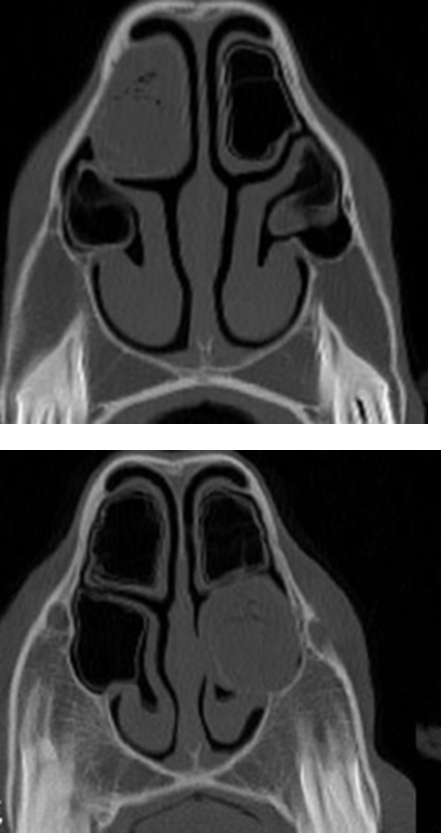

What is being indicated in these images?

Conchal bullae —> air filled but can become infected

then form dorsal & ventral conchae